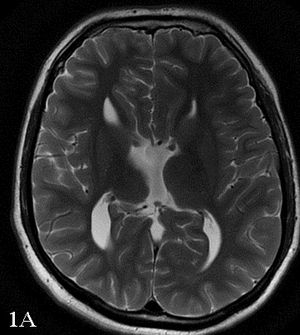

30-year-old male presented with nonspecific headaches.